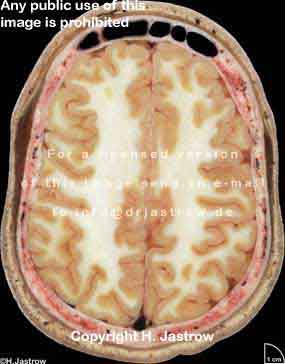

Visible Human male: Sectio transversalis 1058